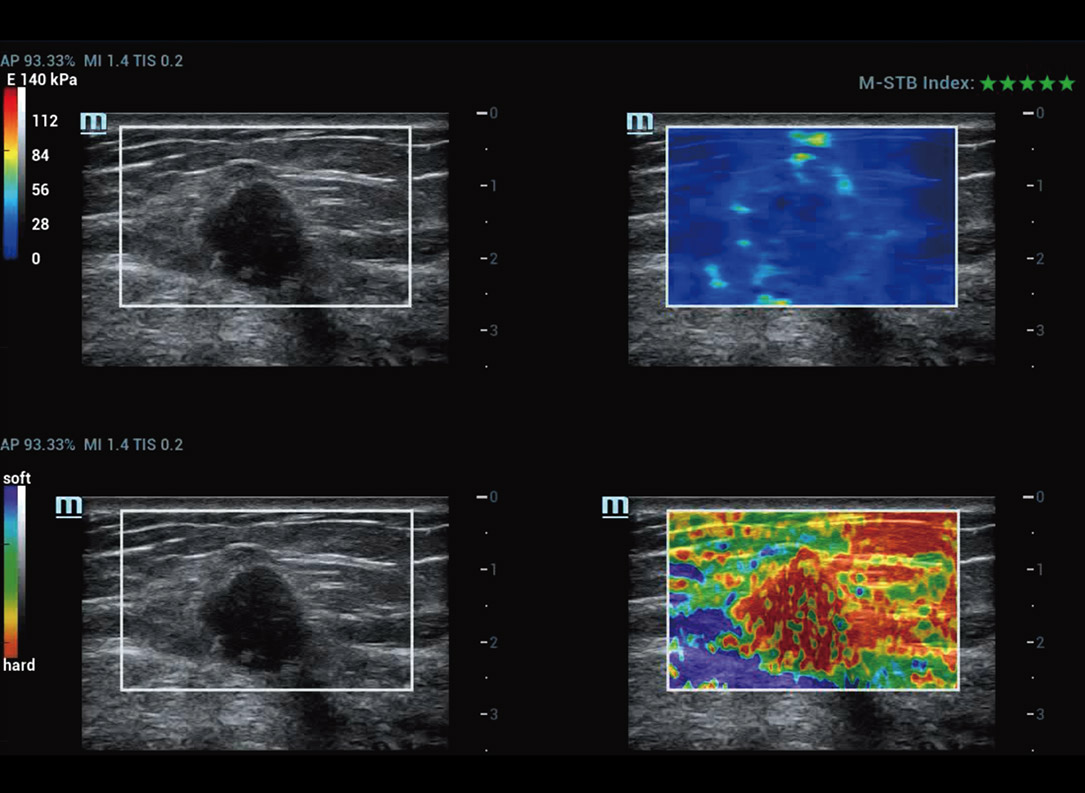

M-Ref. E Compare

M-Ref. E Compare ã Tumor maligno de mama

M-Ref. E Compare oferece suporte û exibi??o tanto da elastografia por deforma??o em tempo real quanto da STE em um û¤nico plano para avalia??o da rigidez do tecido.

E Compare ã Massa mamûÀria no L15-3WU